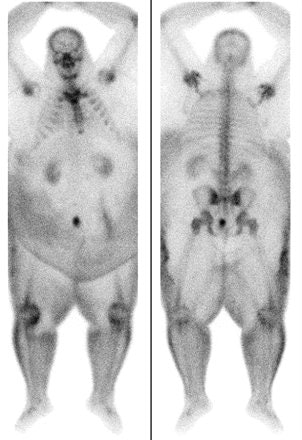

| Technetium-99m bone scans in 60-year-old man with suspected osteomyelitis. Photon scatter and soft-tissue attenuation limit image quality. Uppot RN, Sahan DV, Hahn PF, Gervais G and Peter R. Mueller PR, "Impact of Obesity on Medical Imaging and Image-Guided Intervention" (AJR 2007; 188:433-440). |